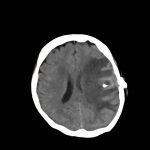

転移性脳腫瘍

断層撮影

手術前1

手術後

No.’13_126 手術前1

No.’13_126 手術後